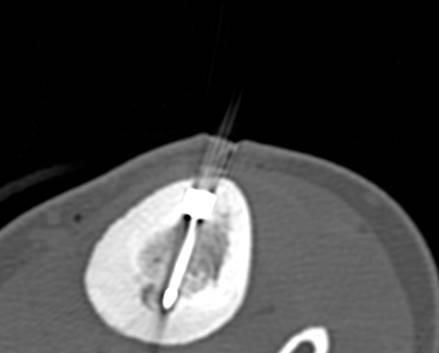

RFA zur Therapie des Osteoidosteoms

Das Osteoidosteom ist ein gutartiger, jedoch sehr schmerzhafter Knochentumor, der bevorzugt bei jüngeren Patienten auftritt. Die Radiofrequenzablation (RFA) hat sich in den letzten Jahren zu einer zuverlässigen, minimalinvasiven Therapieoption bei der Behandlung des Osteoidosteoms entwickelt und wird seit über 15 Jahren an der Uniklinik Tübingen angewandt.

Abbildung: Osteoidosteom (Pfeil) im Schienbein bei einem jungen Patienten. Unter CT-Bildgebung wird ein spezieller Applikatoren unter CT-Bildgebung in das Osteoidosteom eingebracht. Durch Hitze wird dieses effektiv und dauerhaft zerstört.